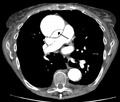

Computed tomography

Computed tomography angiography is a fast, noninvasive test that gives an accurate three-dimensional view of the aorta. These images are produced by taking rapid, thin-cut slices of the chest and abdomen, and combining them in the computer to create cross-sectional slices. To delineate the aorta to the accuracy necessary to make the proper diagnosis, an iodinated contrast material is injected into a peripheral vein. Contrast is injected and the scan performed using a bolus tracking method. This type of scan is timed to an injection to capture the contrast as it enters the aorta. The scan then follows the contrast as it flows through the vessel. It has a sensitivity of 96 to 100% and a specificity of 96 to 100%. Disadvantages include the need for iodinated contrast material and the inability to diagnose the site of the intimal tear.